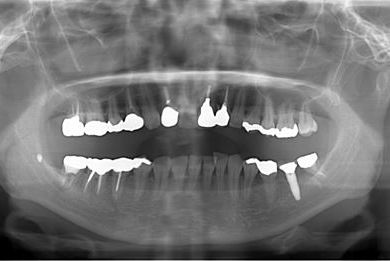

インプラントの症例写真 IMPLANT

骨再生インプラント治療+セラミック治療

| カテゴリー | 【インプラント治療】【セラミック治療】 | ||||||||||||||||||||||||||||||||

| 性別/年齢 | 女性 / 48歳 | ||||||||||||||||||||||||||||||||

| 主訴 | 他の歯科で、前歯の差し歯が折れたところにインプラントをすすめられているので、費用や期間など知りたい。 | ||||||||||||||||||||||||||||||||

| 治療方針 | 骨再生法により、インプラント治療を可能にする。 | ||||||||||||||||||||||||||||||||

| 治療内容 | インプラント1本、メタルボンドセラミッククラウン2本、GBR | ||||||||||||||||||||||||||||||||

| 総治療費 | 618,660円 | ||||||||||||||||||||||||||||||||

| 治療期間 | 9ヶ月 |